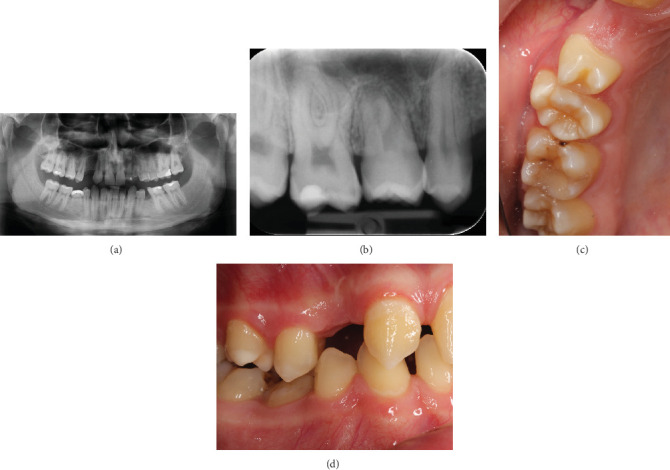

本病例报告报告了由于受术者骨容量不足,牙齿移植和无移植物窦提升是如何结合的。一颗未出牙的智齿被自动移植以取代缺失的上前磨牙。首先,将供牙暴露并轻轻移动。在受体部位,上颌窦下有一薄层骨。侧窗技术用于窦内提升。在提升窦底粘膜后,准备骨以匹配供体牙的尺寸。粘膜轻度穿孔。供体牙移至受体位置,颊根部分骨覆盖缺失。移植的牙齿用缝线固定。在4年的随访对照中,移植牙完全萌出,无任何临床或影像学病理征象。如果移植供牙的牙周韧带处理得当,可以保存和促进牙槽骨的生长。在随访中,供体牙的牙根周围明显形成了新骨。在上颌前磨牙区成功移植发育中的牙齿是可能的,尽管最初的骨容量不足。

This case report reports how tooth transplantation and a graft-free sinus lift were combined due to insufficient bone volume at the recipient site. An unerupted wisdom tooth was autotransplanted to replace a missing upper premolar. First, the donor tooth was exposed and gently mobilized. At the recipient site, there was a thin layer of bone under the maxillary sinus. The lateral window technique was used in the sinus lift. After elevating the mucous membrane of the sinus floor, the bone was prepared to match the measures of the donor tooth. The mucous membrane was slightly perforated. The donor tooth was moved to the recipient site, and the buccal root partially lacked bony coverage. The transplanted tooth was fixated with sutures. At the 4-year follow-up control, the transplanted tooth was fully erupted without any clinical or radiographical signs of pathology. If the periodontal ligament of the transplanted donor tooth is delicately handled, it can preserve and facilitate the growth of the alveolar bone. During follow-up, it was obvious that new bone had formed around the roots of the donor tooth. It is possible to successfully transplant a developing tooth in the maxillary premolar region, although the initial bone volume is insufficient.